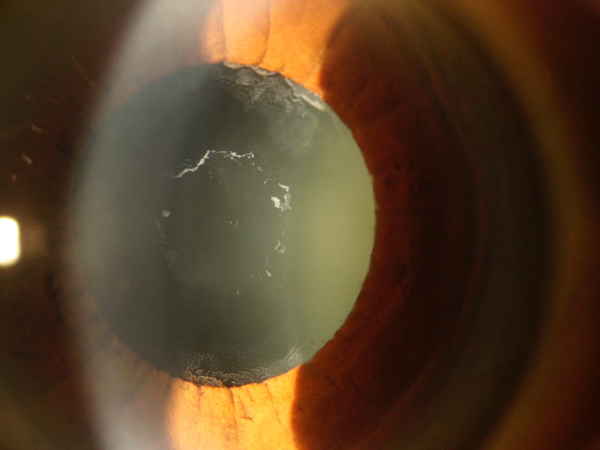

Pseudoexfoliación capsular